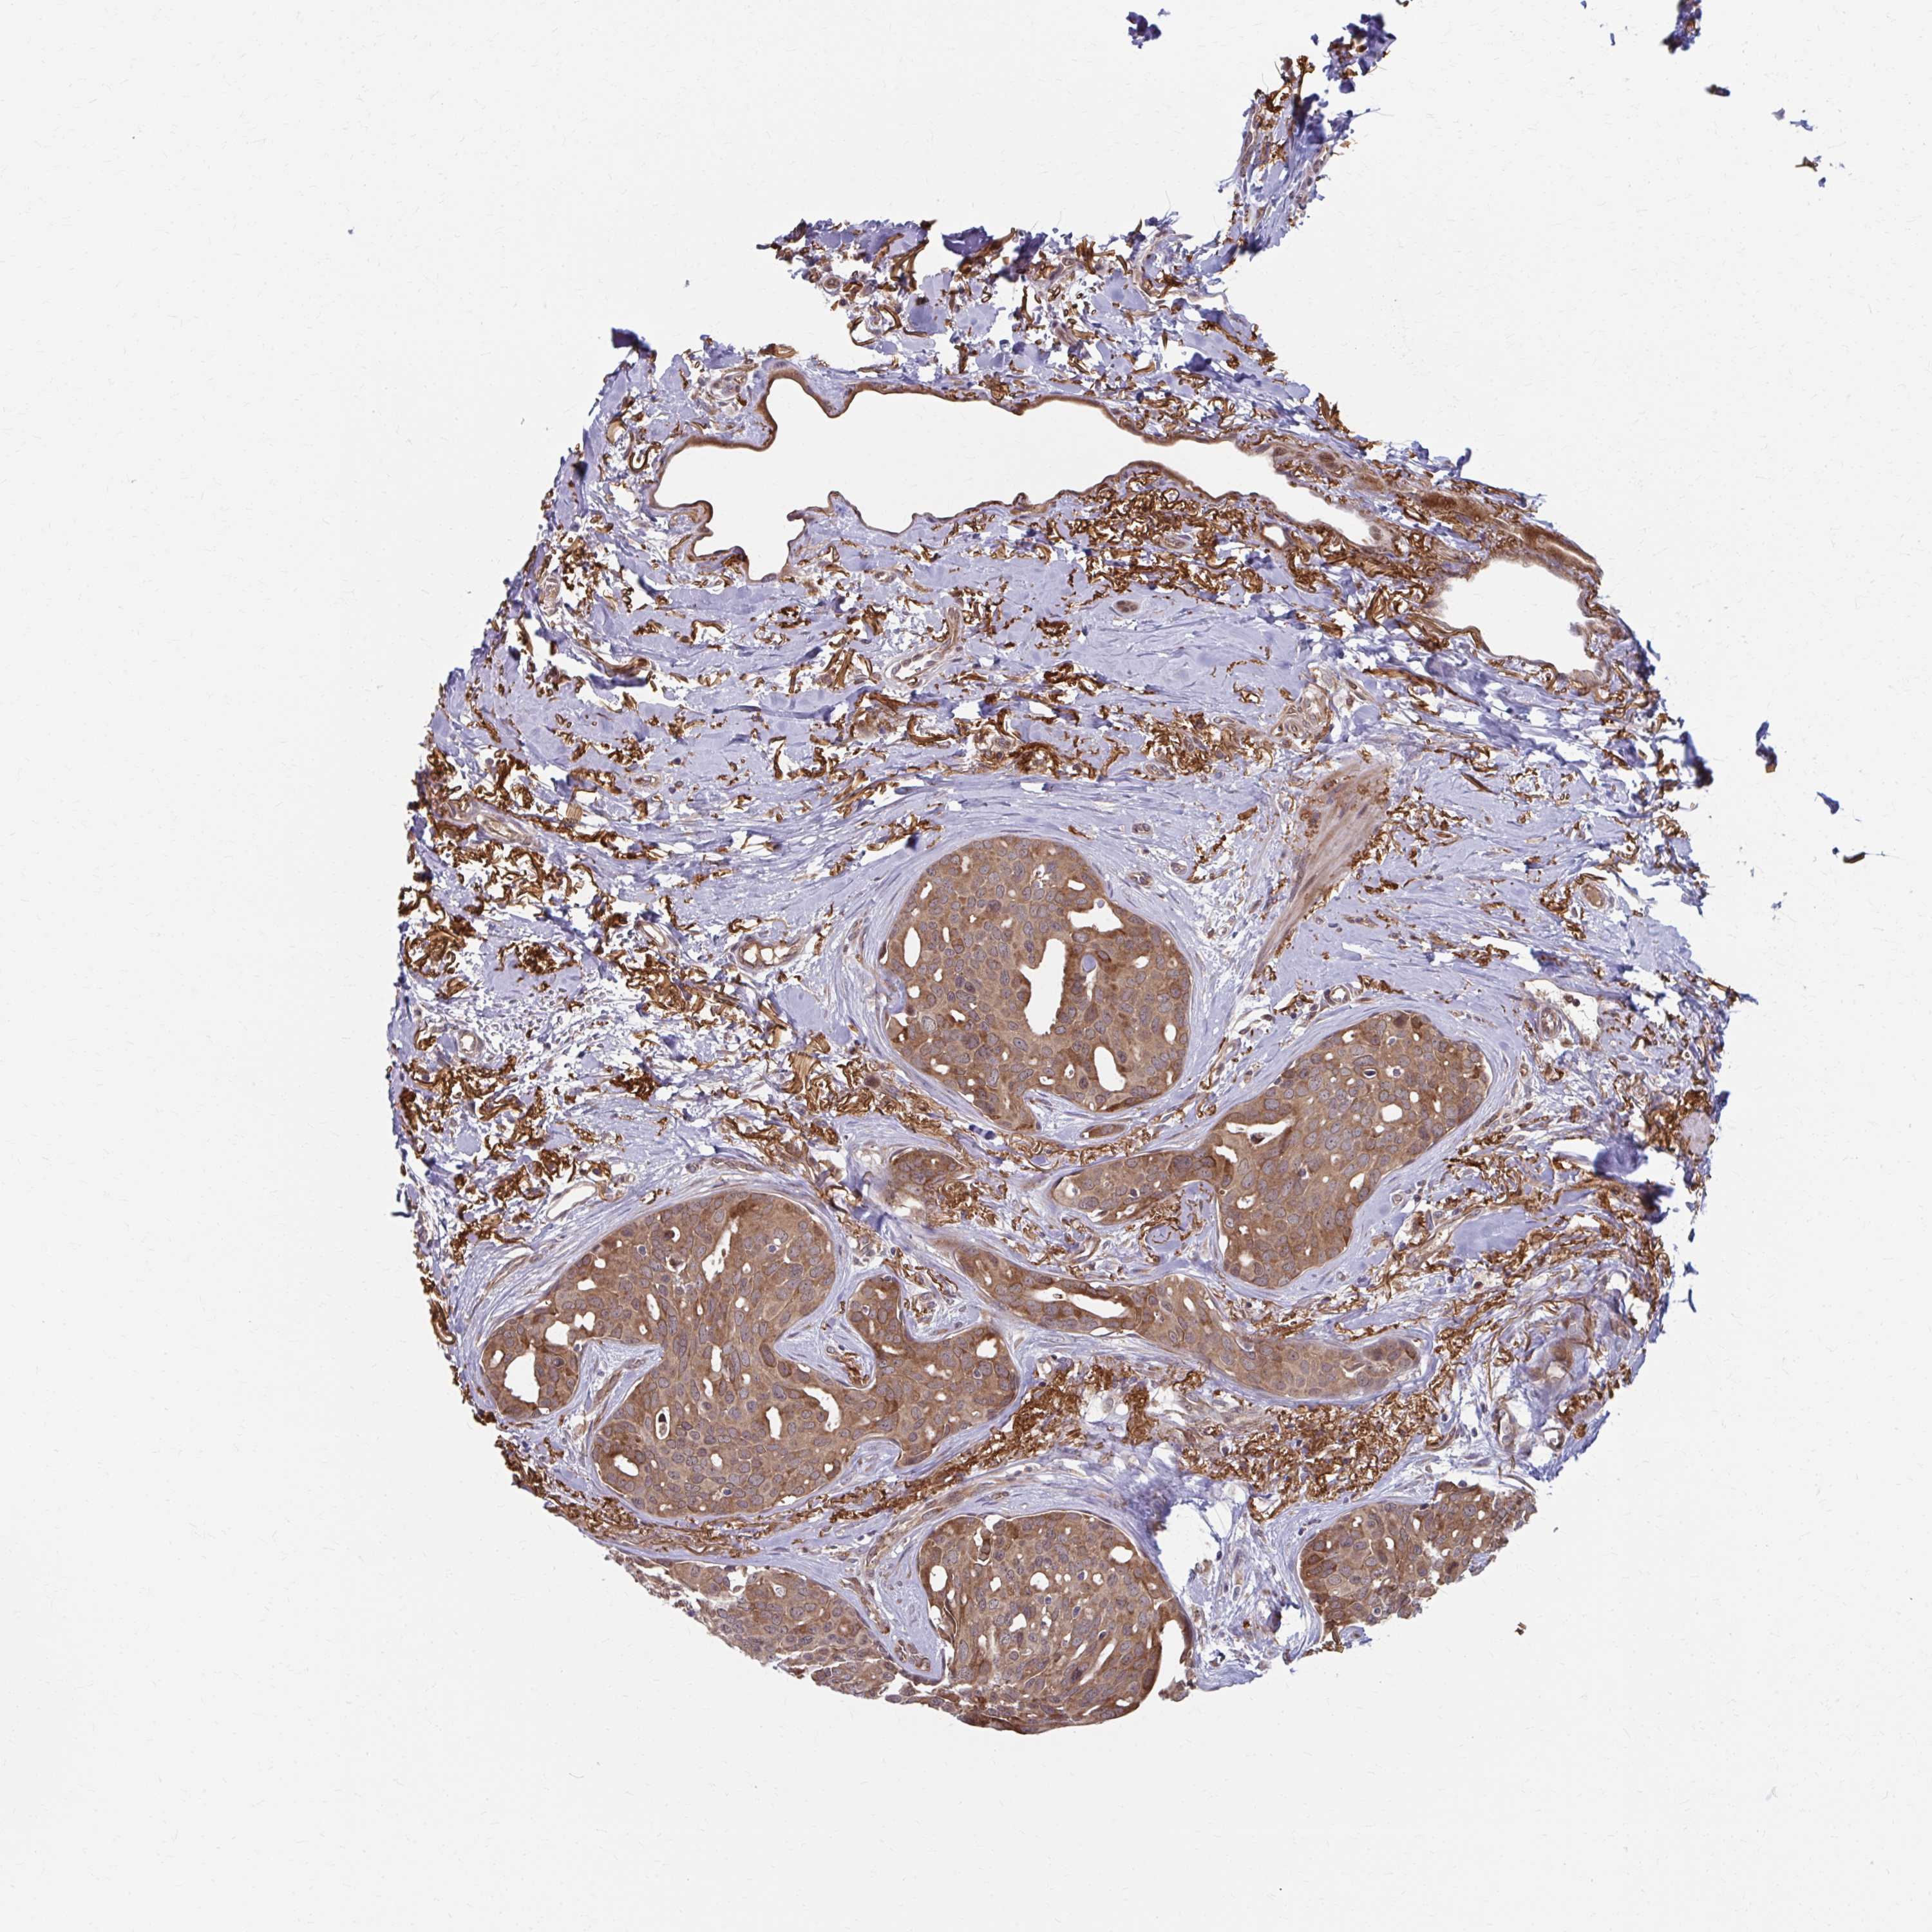

CANCER BREAST CANCER Show tissue menu

BRCA TCGA BRCA VALIDATION PROTEIN EXPRESSION